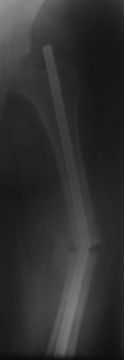

Уважаемые коллеги.  Обратилась б-ная  Д, 32 г  с  рефрактурой  с/з

диафиза левой  бедренной  кости  со  сломанным  штифтом  и  с 20-ти

дневным  новорожденным  ребенком  на  руках.

Со  слов  10.11.05 г. оперирована  в  БСМП ,  видимо  произведена

ОИМО  штифтом  ЦИТО,  в то время  тоже  была  беременной,  перелом

якобы  долго не срастался, потом  ходила  с палочкой,  после  выкидыша

повторно  забеременела,  поправилась  на  14кг  и  где-то  в середине

августа  заметила  отечность и постепенное  искривление бедра,  к

травматологам  не  обратилась  т.к.  её  цель  была  сначала  родить

ребенка.

При  осмотре  отмечается  умеренная  отечность, рекурвация  и

варусное  искривление  на уровне  с/з  диафиза  бедра, патологической

подвижности явно не определяется (ну тугая), умеренная  болезненность

при пальпации, движение  в  коленном  суставе  почти в полном  объеме .

Р-снимок  пока  только  один, б-ная  отправлена  гематологам.